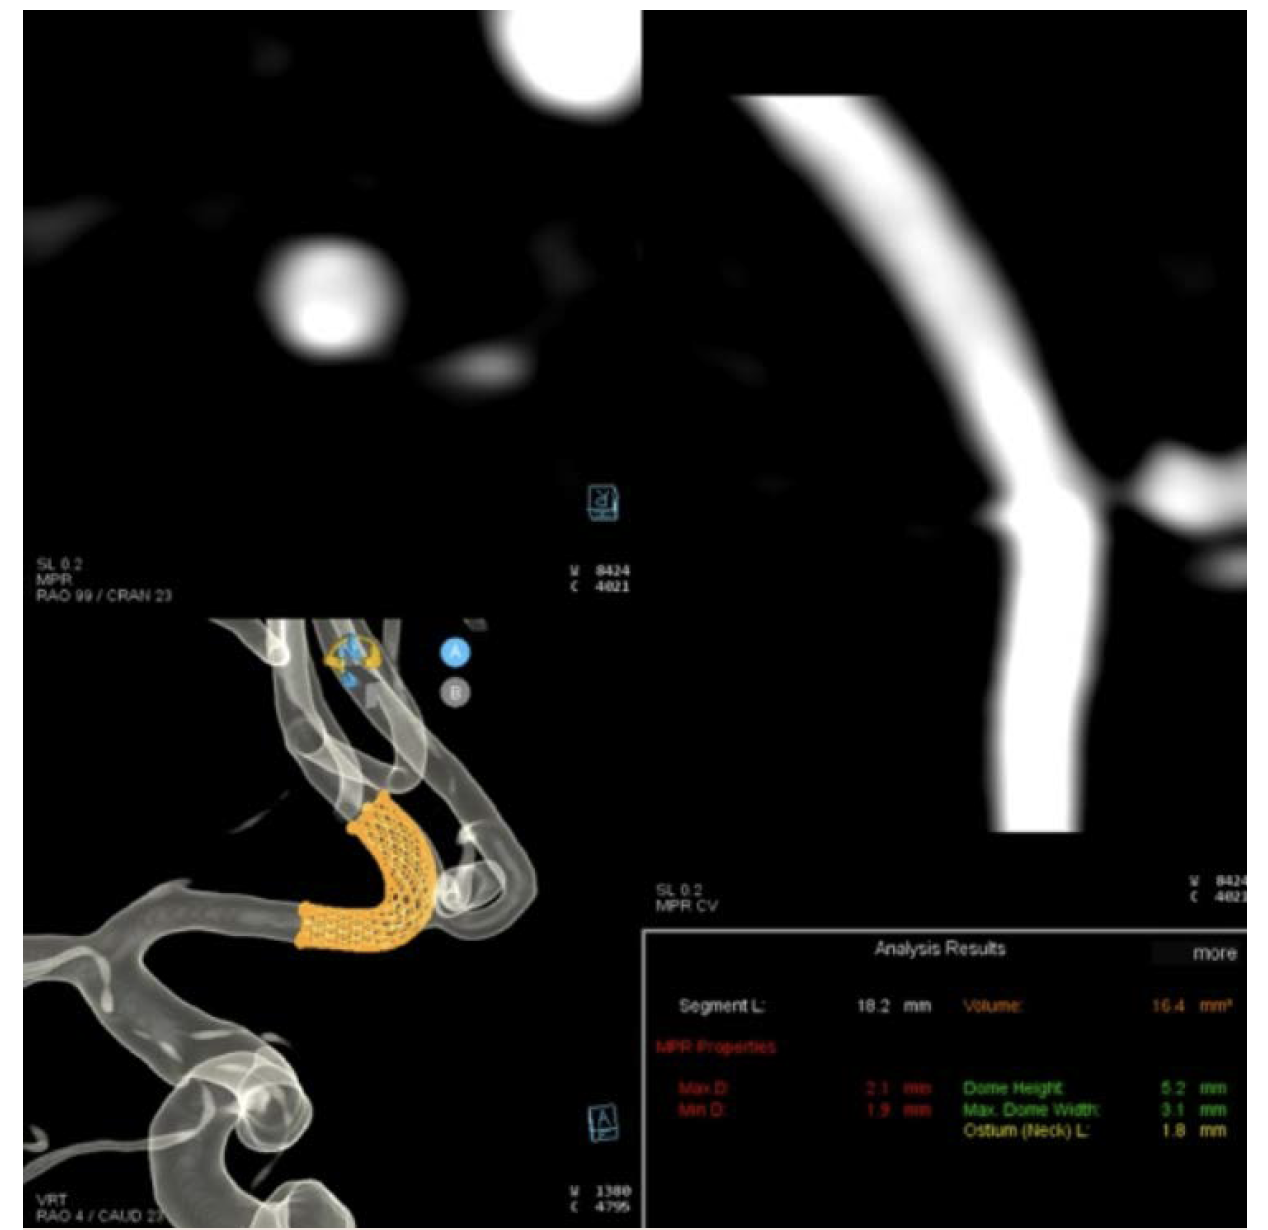

Workflow on the ARTIS icono is exceptional (Figure 1). I start with a biplane angiogram of the entire head. I then do a 4-second DSA 3D acquisition, adjusting the timing of the delay based on the timing of complete opacification on the planar imaging. The 3D reconstruction can then be used to perform syngo Neuro Aneurysm Analysis (Siemens Healthcare AG) to better understand the arterial diameter(s) and start to plan the pipeline construct, both in diameter and length as well as number of devices. The accuracy of the Aneurysm Analysis diameter is excellent and has given us confidence in device diameter selection that we didn’t have previously (Figure 2).

Often, arteries are ovalized and the average diameter provided by the machine has worked very well for us. In addition, the length measured through curvilinear space has enabled us to use shorter devices—almost exclusively 10 and 12 mm. Previously, we would make 1 linear measurement, then move the 3D, make a second measurement, then add 2 mm for margin of error. Often, the stent sizes would end up in the 14- to 16-mm range. Aneurysm Analysis has therefore had a tremendous impact on the way we select devices (Figure 3).

The aneurysm analysis tool was utilized to assess arterial diameters in both the distal and proximal landing zones as well to choose a stent length for the first stent and make an initial plan for the construct (Figure 12).